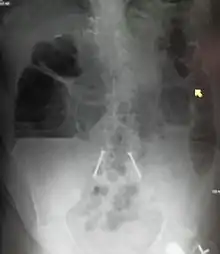

The main diagnostic tools are blood tests, X-rays of the abdomen, CT scanning, and ultrasound. If a mass is identified, biopsy may determine the nature of the mass.

Radiological signs of bowel obstruction include bowel distension and the presence of multiple (more than six) gas-fluid levels on supine and erect abdominal radiographs. Ultrasounds may be as useful as CT scanning to make the diagnosis.[13]

Contrast enema or small bowel series or CT scan can be used to define the level of obstruction, whether the obstruction is partial or complete, and to help define the cause of the obstruction. The appearance of water-soluble contrast in the cecum on an abdominal radiograph within 24 hours of it being given by mouth predicts resolution of an adhesive small bowel obstruction with sensitivity of 97% and specificity of 96%.[14]